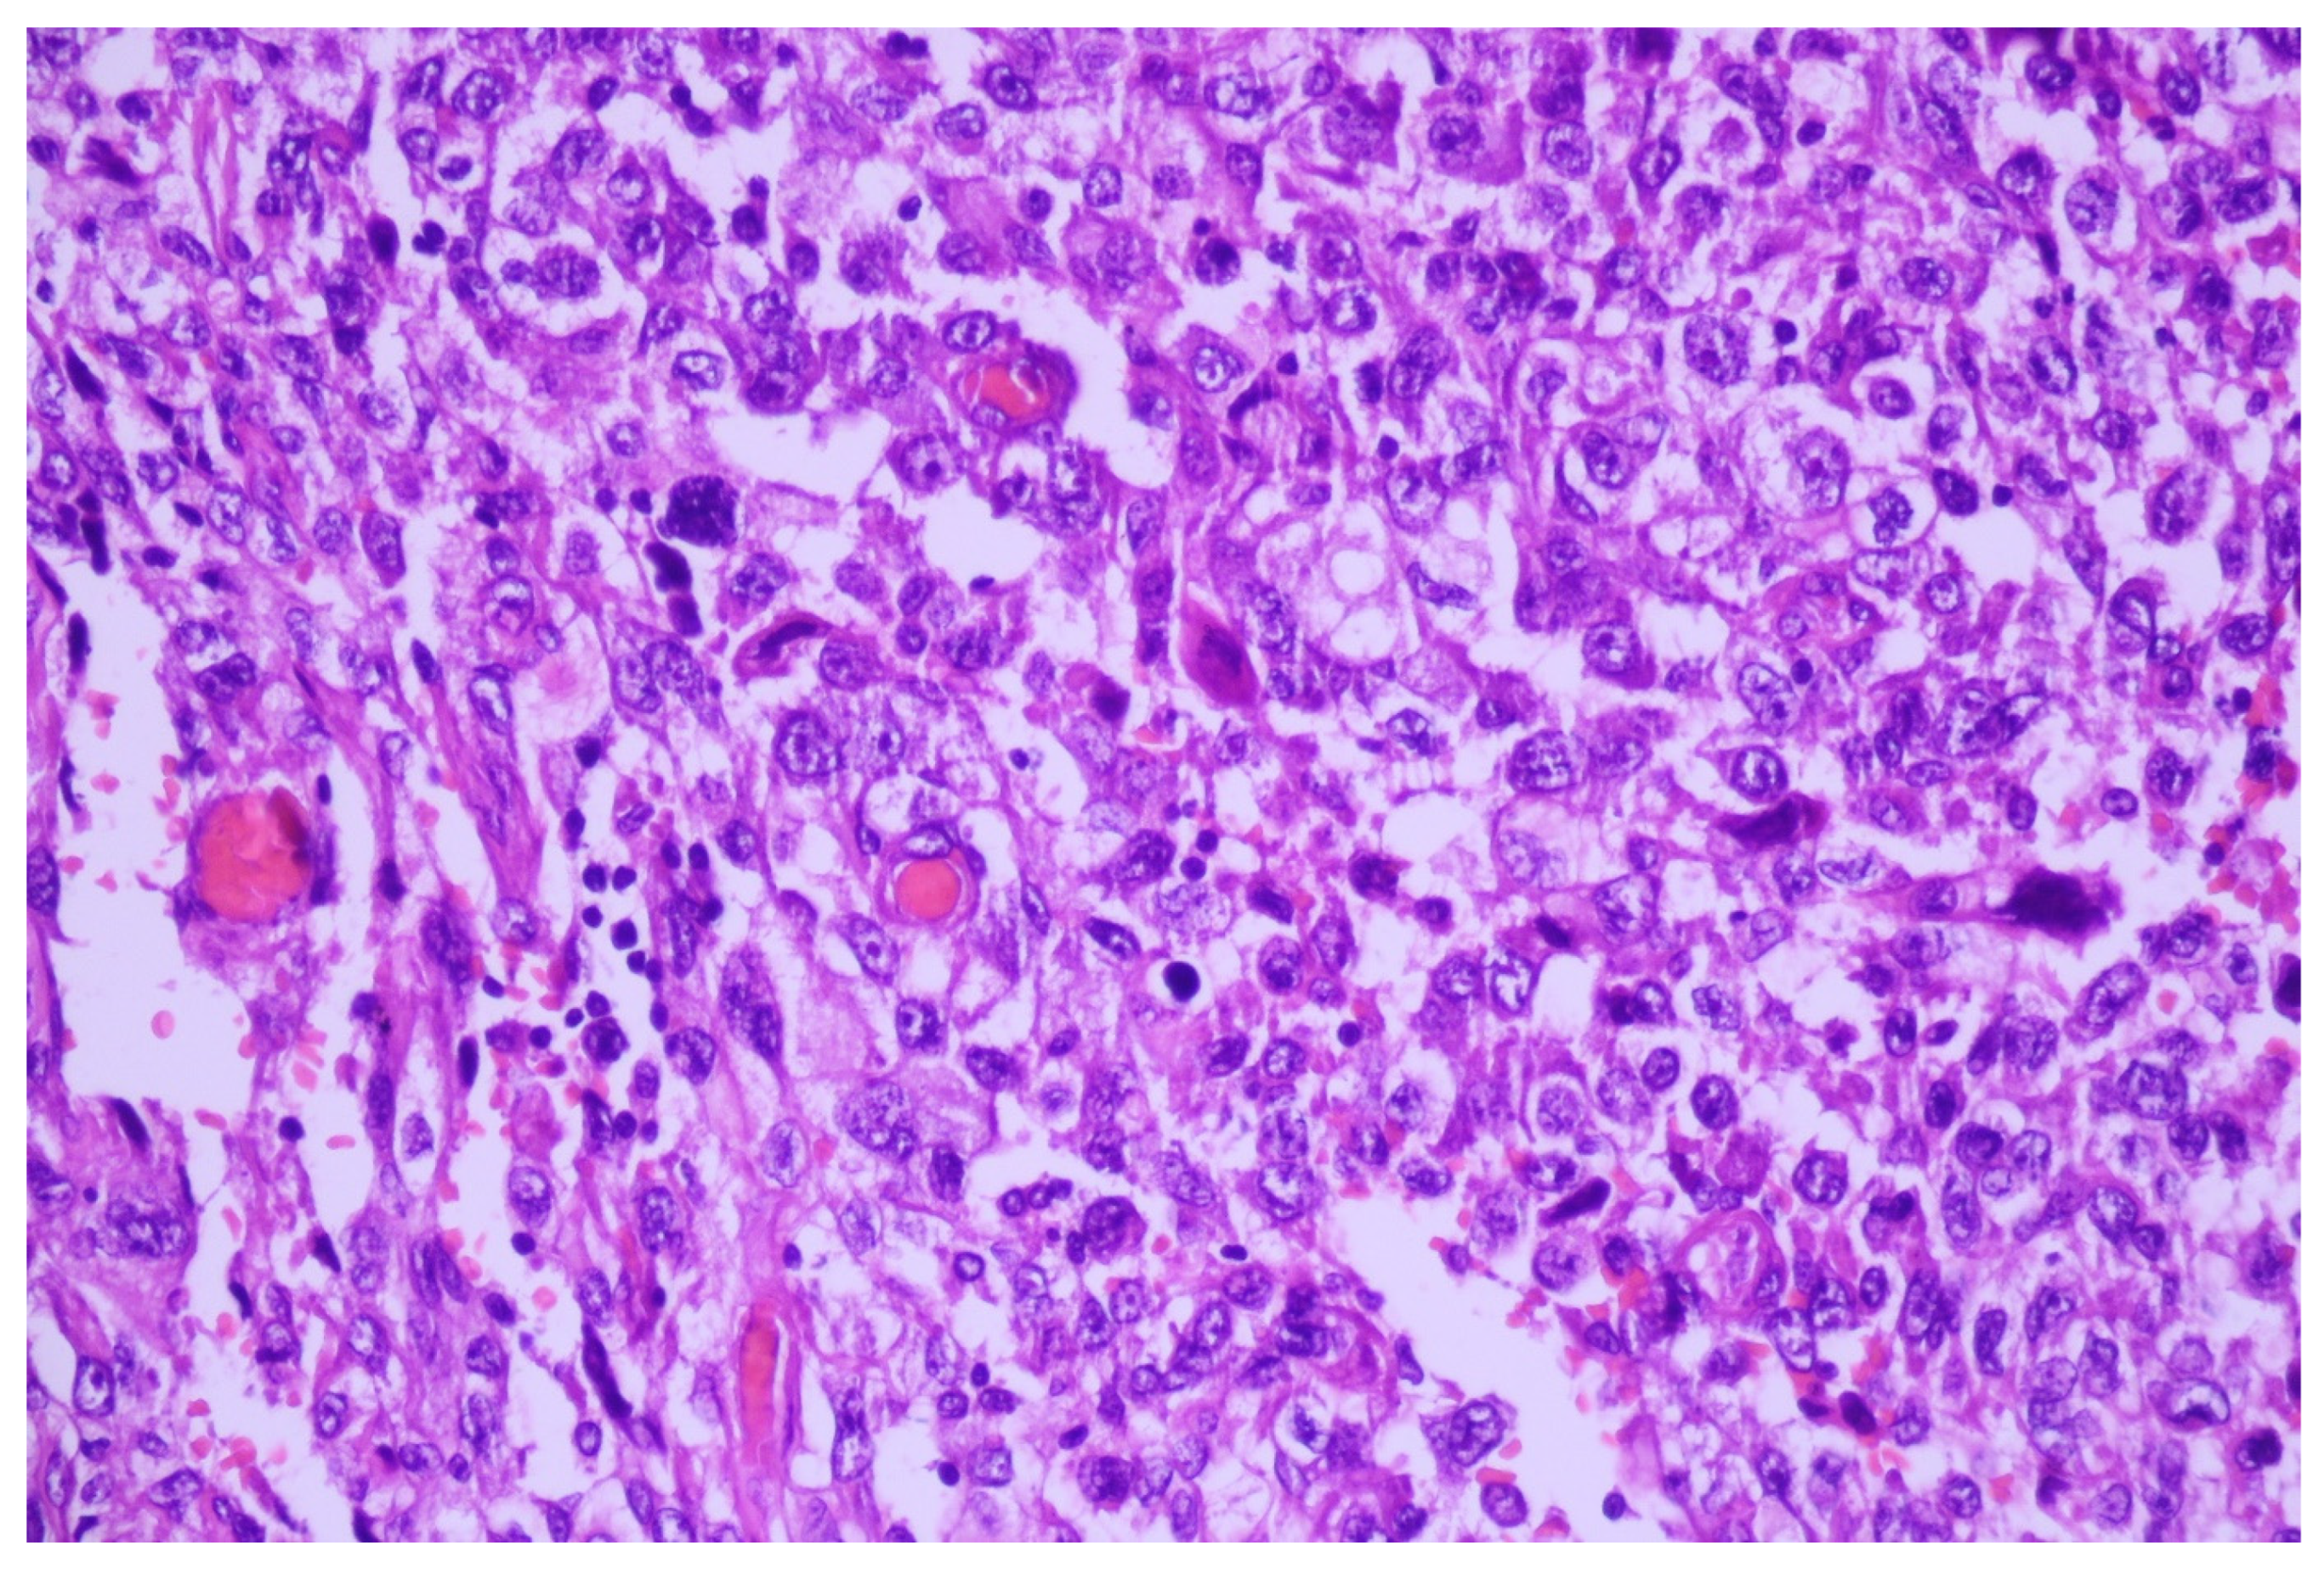

3.1. Case No. 1

3.2. Case No. 2

3.3. Case No. 3

3.4. Case No. 4

4.2.3. Signet Ring Features in Lung Carcinoma

4.2.4. Clear Cell Features in Lung Carcinoma